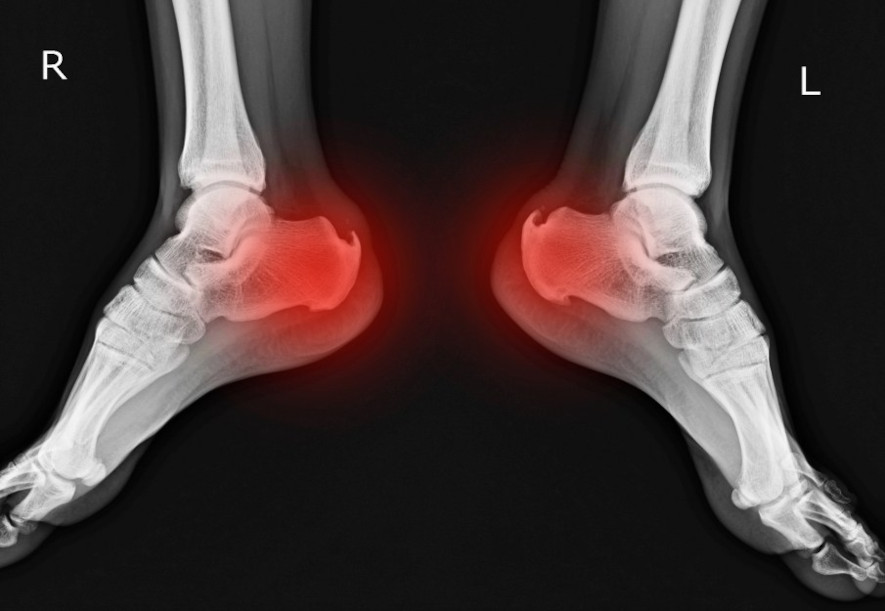

Haglunds häl, eller Haglunds sjukdom, Haglunds deformitet, yttrar sig som värk och smärta kring bakre delen av hälen mot hälsenan. Smärtan kommer av att det bakre hälbenet luckrats upp och en slemsäcksinflammation på nedre delen av achillessenan, vilket visas i bilden här nedan.

Bild som visar smärtområdet vid Haglunds häl.

Bild som visar smärtområdet vid Haglunds häl.